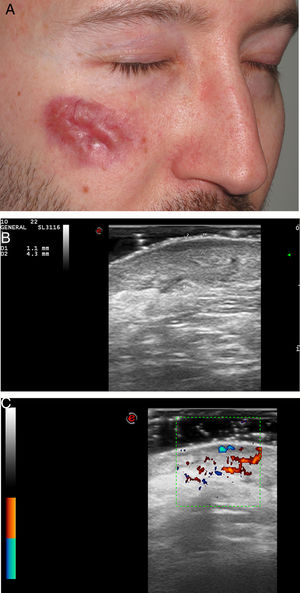

Se incluyó a 5pacientes (4 hombres y una mujer) con 6lesiones en total, con una mediana de edad de 67 años (rango: 39-71) y una biopsia comprobada de granuloma facial. En 3pacientes las lesiones estaban localizadas en la cara, en uno en el cuero cabelludo, en otro en la oreja y en otro en el ombligo. La mayoría de los pacientes habían sido tratados mediante diferentes tratamientos sin obtener mejoría clínica (tabla 1). En la evaluación ecográfica, el granuloma facial se presentó como una lesión hipoecoica y heterogénea situada en la dermis e hipodermis con un aumento de la vascularización en el modo color Doppler (figs. 1-2). Casi todas las lesiones (5/6) estaban mal definidas. En 5 de los granulomas faciales se observó una banda hipoecoica/anecoica subepidérmica marcada. Una lesión (caso 5, nariz) presentó un refuerzo posterior. No hubo diferencias significativas en las características ecográficas entre los granuloma facial faciales y extrafaciales (tabla 1).

| 1 | H/39 | 5 | Mejilla derecha | Corticosteroides tópicos, hidroxicloroquina, dapsona, láser, tacrolimus tópico | Presencia de zona de Grenz Infiltrado inflamatorio denso formado principalmente por eosinófilos, escasos histiocitos, linfocitos y ocasionalmente por células plasmáticas | Lesión hipoecoica, heterogénea y mal definida en dermis e hipodermisBanda subepidérmica hipoecoica | Aumento de la vascularizaciónVasos en la dermis con un diámetro superior a 0,63mm |